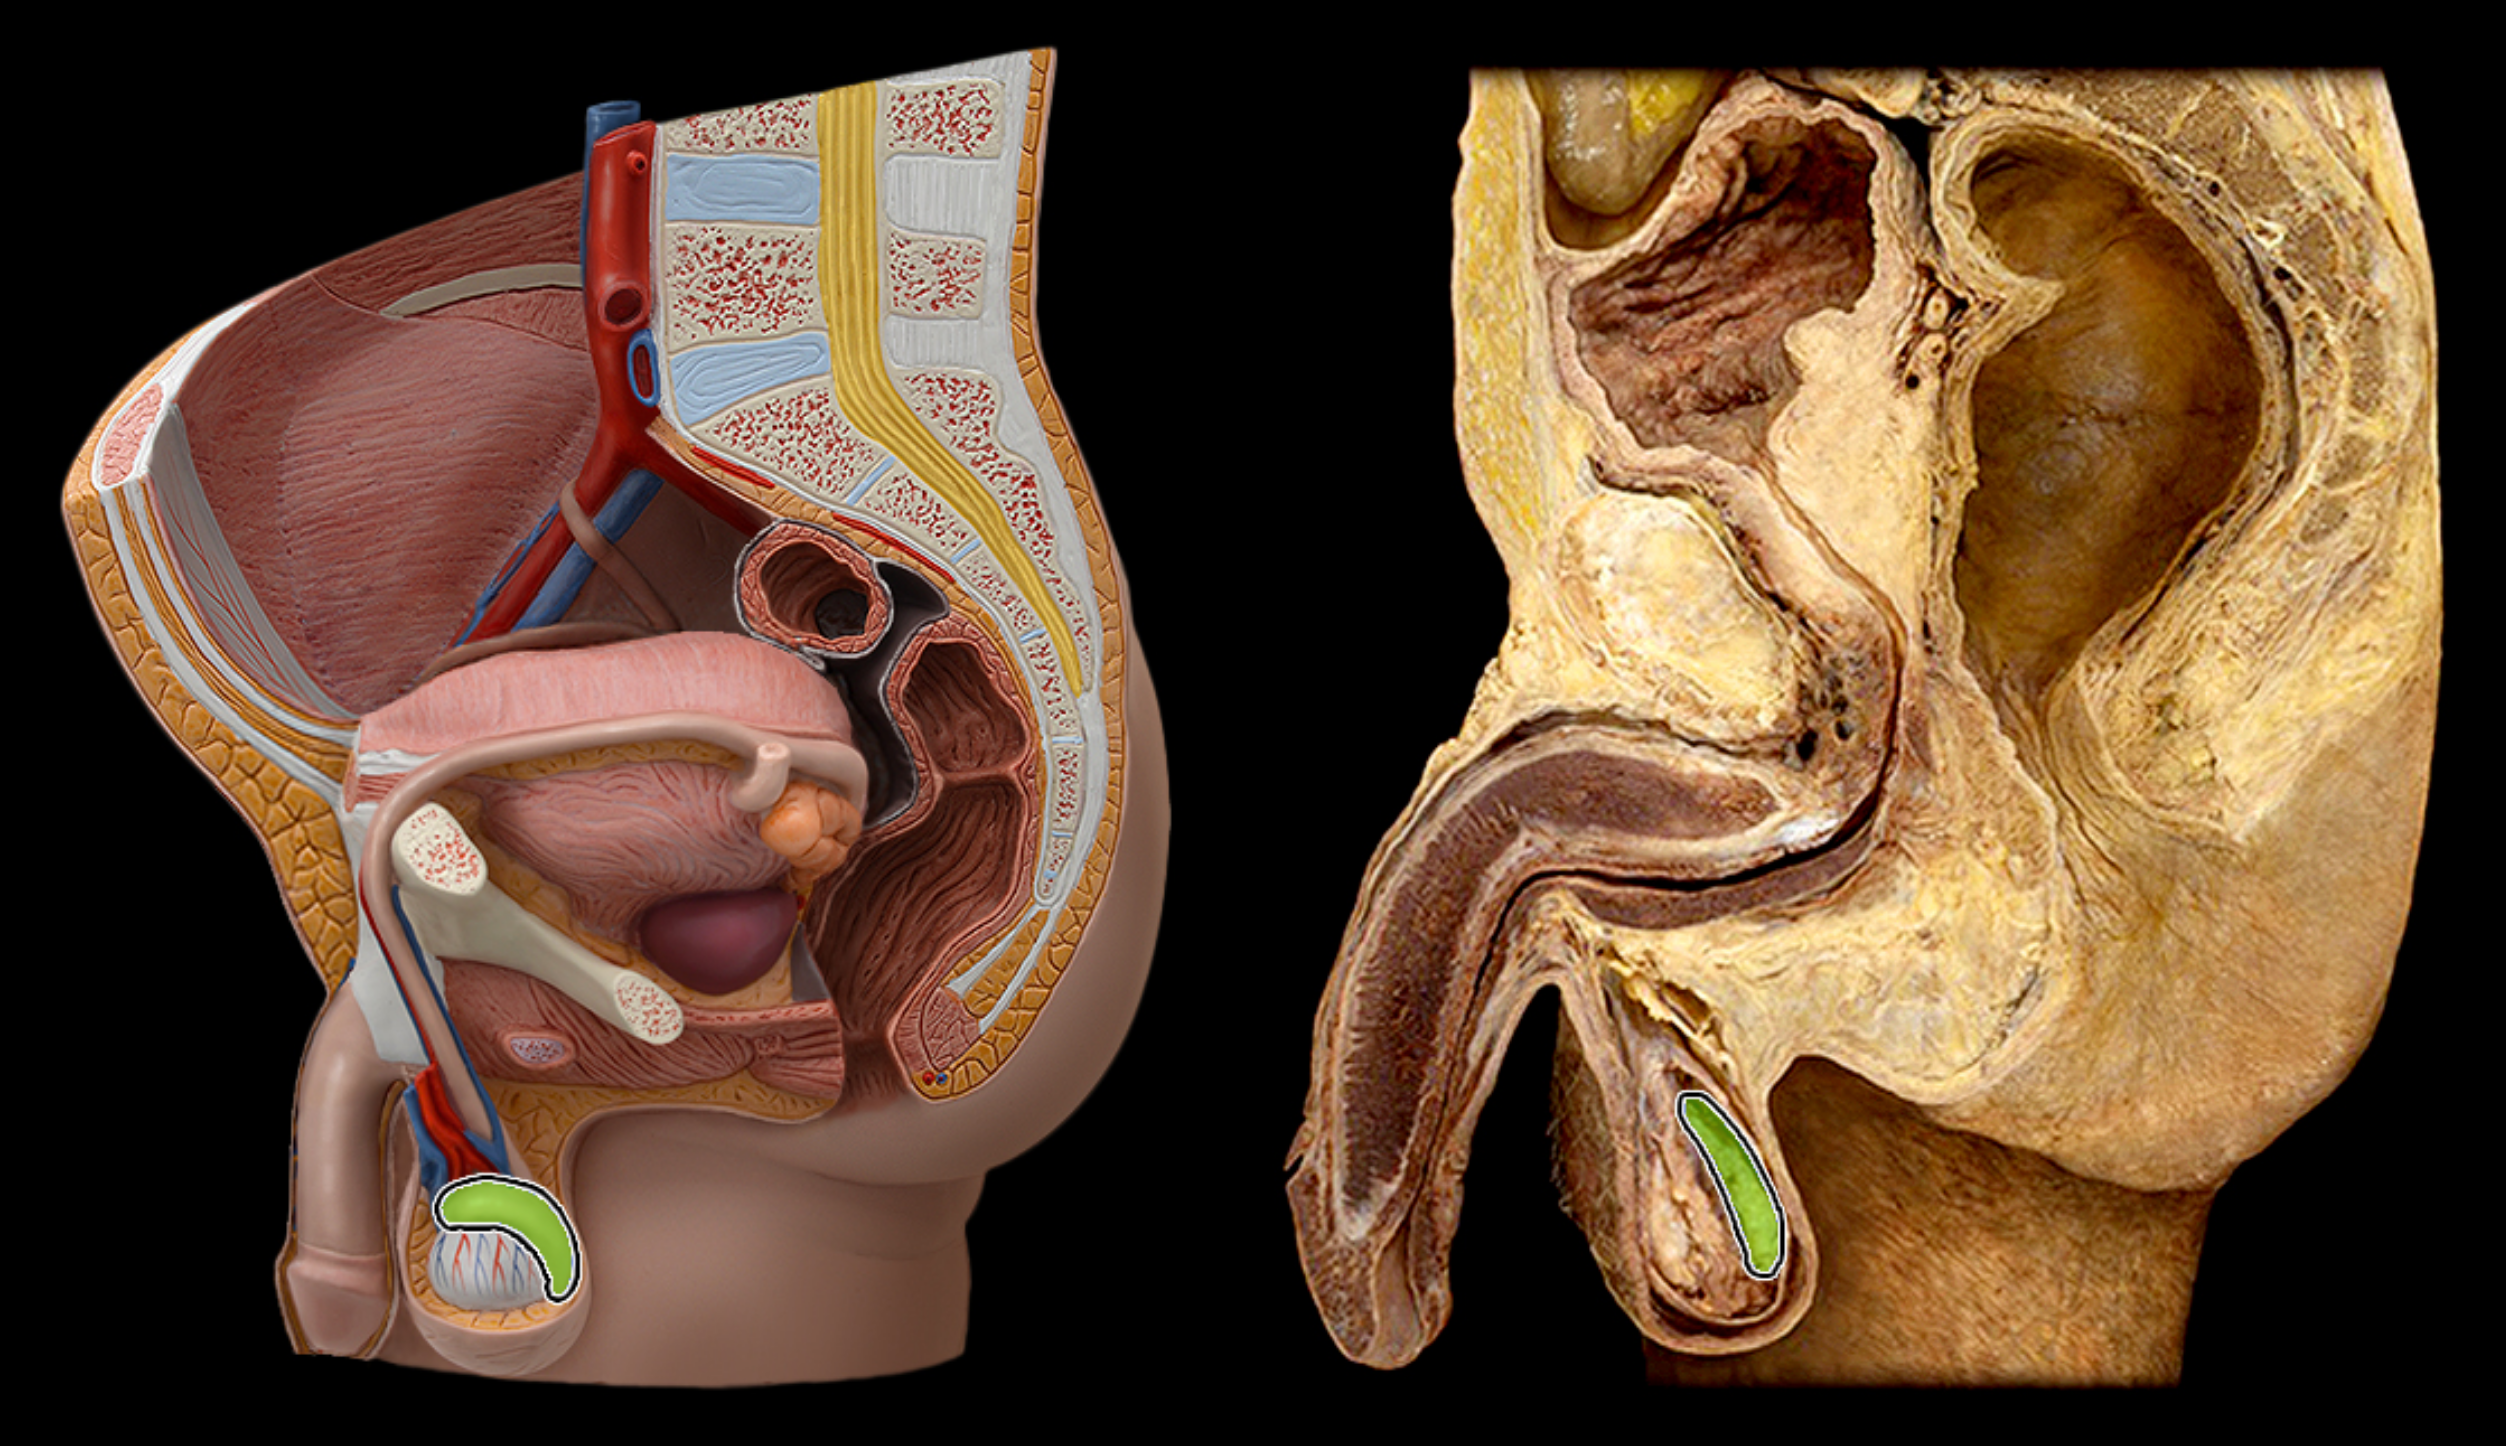

Vas deferens (ductus deferens)

Ejaculatory duct

Seminal vesicle

epididymis